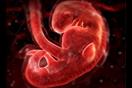

يعتقد البعض أن نمو الطفل يبدأ خلال فترة الرضاعة، ولكن فترة ما قبل الولادة تعتبر أيضًا جزءًا مهمًا من عملية النمو، حيث تحدث عملية التطور قبل الولادة في ثلاث مراحل رئيسية.

ويُعرف الأسبوعان الأول والثاني بعد الحمل بالمرحلة الجرثومية، بينما يُطلق على الفترة ما بين الأسبوع الثالث حتى الأسبوع الثامن بالمرحلة الجنينية، في حين يُعرف الوقت من الأسبوع التاسع حتى الولادة باسم فترة الجنين.

يحدث الإخصاب عندما يلتقي الحيوان المنوي بالبويضة ويخترقها، وهو ما يؤدي إلى حدوث الحمل، وفي هذه اللحظة، يكتمل التركيب الجيني للجنين، بما في ذلك الجنس.

وفي غضون ثلاثة أيام تقريبًا بعد الحمل، تنقسم البويضة الملقحة بسرعة كبيرة إلى عدة خلايا، تمر عبر قناة فالوب إلى الرحم، حيث تتصل بجداره، كما تبدأ المشيمة المسؤولة عن تغذية الطفل مستقبلًا في التكون.